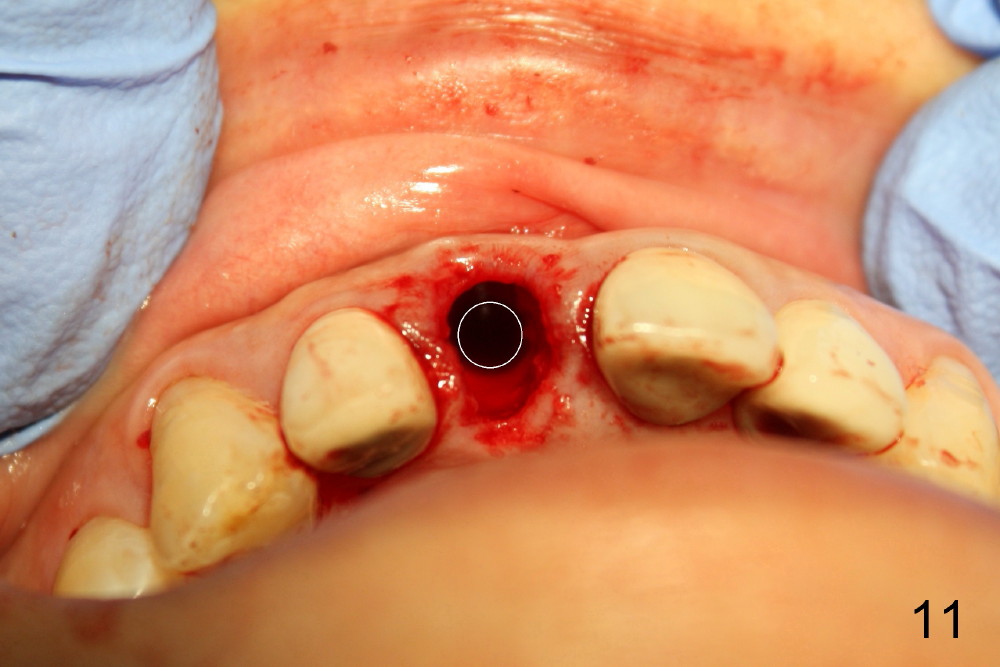

图六是CT扫描,显示中切牙以及牙槽骨矢状切面(B:颊侧)。拔牙后,如果我们沿着牙齿长轴钻洞(图七:红长箭头),势必将使菲薄的颊侧骨板穿破(X),其实牙槽窝舌侧(L)有很多骨质。钻洞必须在舌侧骨板中点开始(箭头),但是舌侧骨板是一个斜坡,起初钻洞必须与舌侧骨板垂直(图八:箭头),否则钻头会打滑。一旦钻头初步进入骨质,必须改变钻头方向:沿着牙槽骨长轴前进(图九:长箭头),否则舌侧骨板也会穿孔(沿原来短箭头)。边钻洞边用拇指和食指握住颊舌侧骨板,把握钻头方向。图十显示上颌中切牙处五乘二十毫米锥形植牙设计。

当我们拔出3.5毫米钻头(图五:最后一个钻头)时,就可以看见在舌侧骨板植牙洞型制备(图十一:圆圈)。图十二,图十三分别显示立刻植牙正面观和切缘观,植牙几乎占据所有牙槽窝空间,不需植骨或者缝线。植牙好像没有侵犯邻牙牙根(图十四,图十五,包括七号牙:侧切牙),其实只要熟悉局部解剖(图六至图十),即刻植牙反而容易进行。图十五虚线代表切牙孔,挺接近植牙(I),术后渗血较多,可能与此有关。除此之外,术后病人恢复很快。